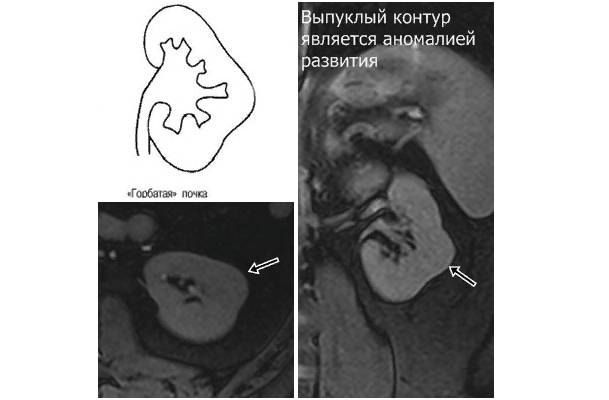

Горбатая (подковообразная) почка – это аномалия, при которой меняется анатомическая форма органа. Чаще всего формируется выпуклое образование с одной стороны, но горбатость может выходить за контуры почки и с обеих сторон.

Деформация бывает разной. Почка может иметь шарообразную, овальную, серповидную форму. Очертания формируются прямые или в виде волн. При диагностическом обследовании выявляются обычные или увеличенные размеры органа.

Если почка имеет деформированную форму, врач проводит дифференциальную диагностику для того, чтобы исключить наличие злокачественного образования.

Для выявления характера выпячивания применяются различные диагностические методы. Самый распространенный – ультразвуковое исследование.

Подробное изучение состояния тканей и сосудов проводится в ходе экскреторной урографии, компьютерной и магнитно-резонансной томографии, гистологического исследования образца тканей.